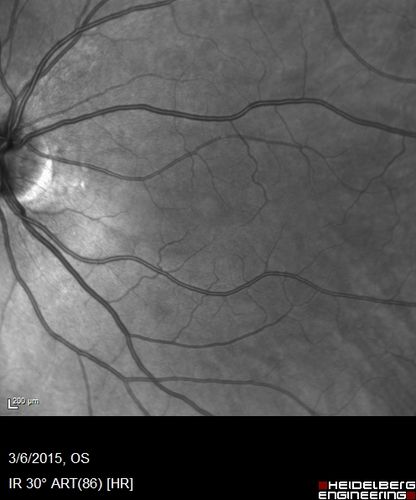

Foveal hypoplasia - aplasia

SD OCT shows persistent plexiform layers in the center of the macula

EXTENDED HPI: He is having some trouble seeing his gadgets (like his watch). He was diagnosed with morning glory syndrome at about 3 yeras old. This last visit you saw fluid under the retina and asked him to come here. The vision is a little worse.

VA OD: Dcc20/40+2 NccJ2-2

VA OS: Dcc20/25-2 NccJ1-2